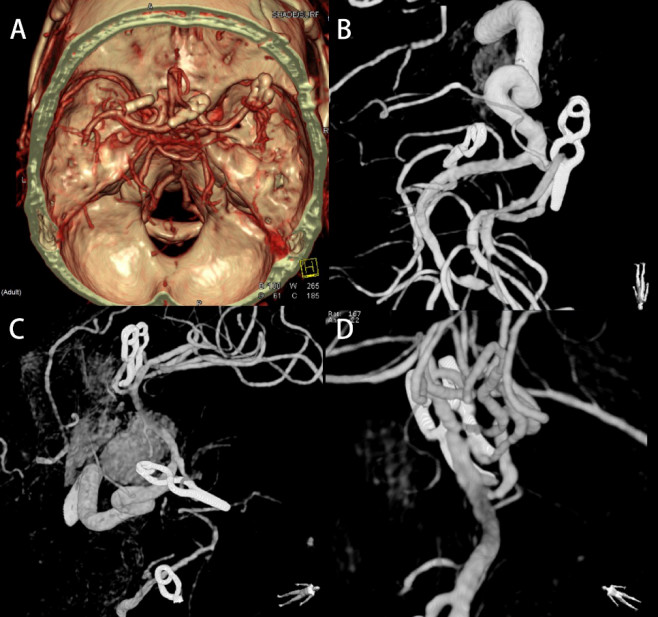

患者术后恢复良好,神志清,双瞳等大等圆,直径约3mm,对光反射敏感,颈软,四肢肌力5级,肌张力不高,病理征阴性。术后复查头颅CTA及DSA见4个动脉瘤夹闭完全无残留,载瘤动脉通畅(图2)。患者目前随访3年余无术后并发症。

图2. 术后CTA(A)及DSA(B、C、D)提示4个动脉瘤夹闭完全无残留,载瘤动脉通畅